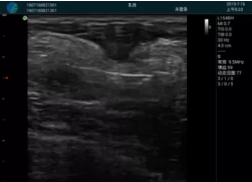

頸動(dòng)脈血流充盈飽滿,無外溢

肝內(nèi)血管顯示清晰,血流敏感無外溢